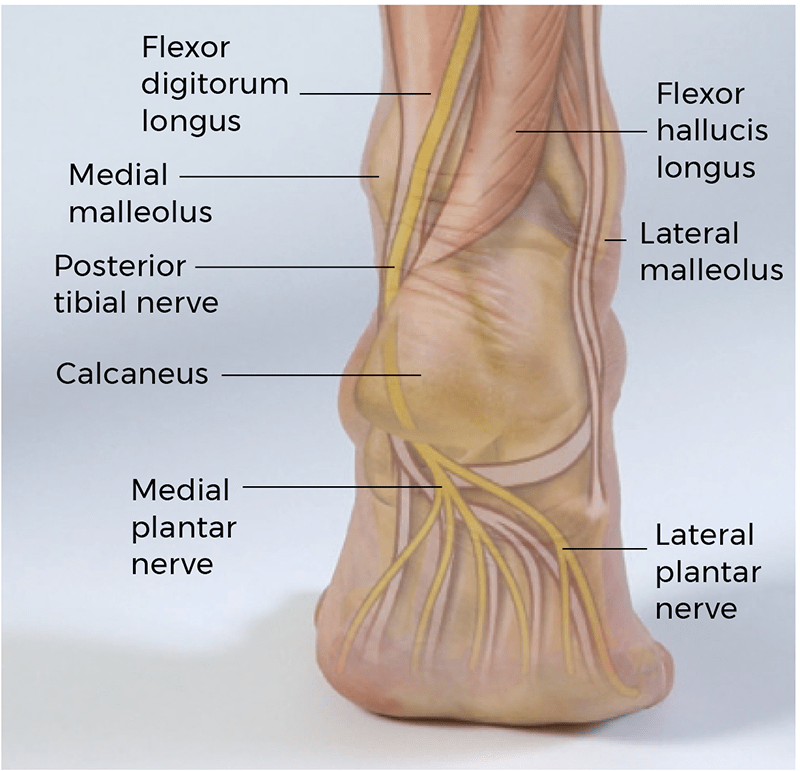

Similar to the carpal tunnel of the wrist, the tarsal tunnel serves as an important passageway for several structures. These include the tendons of the tibialis posterior, flexor digitorum longus (FDL), and flexor hallucis longus (FHL). Running alongside these three tendons are the posterior tibial nerve, artery, and vein. Organized from medial to lateral, the contents of the tarsal tunnel are the tibialis posterior tendon, FDL tendon, posterior tibial artery and vein, posterior tibial nerve, and FHL tendon. The posterior tibial nerve bifurcates within the tarsal tunnel (most common) or just proximal to it (less common) into the medial and lateral plantar nerves.

Both the medial plantar nerve and lateral plantar nerve have both sensory and motor fibers in the foot. Sensory function for the medial plantar nerve includes the medial half of the foot, the first three digits, and half of the fourth. Motor function includes the lumbricals, abductor hallucis, flexor digitorum brevis, and flexor hallucis brevis. Sensory function for the lateral plantar nerve includes the medial calcaneus and lateral heel. Motor function includes the flexor digitorum brevis, quadratus plantae, and abductor digiti minimi.